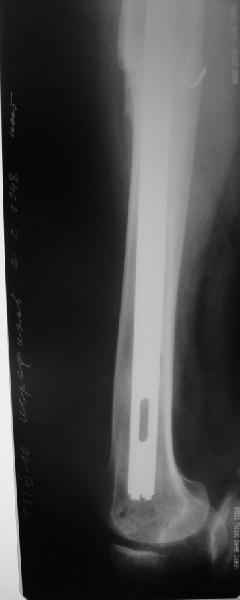

Пациента удалось осмотреть недавно. Достигнутый результат сохраняется. Перелом бедра сросся. Конечность опорная и безболезненная, ходит без трости. Ножка, похоже, реинтегрировалась, как и надеялись. Снимки и фото в приложении. Комментарии приветствуются.

Надо ли что-то делать дальше, как полагаете? Убрать винты? Убрать "удлинитель ножки"? Или оставить все, как есть? Спасибо заранее.